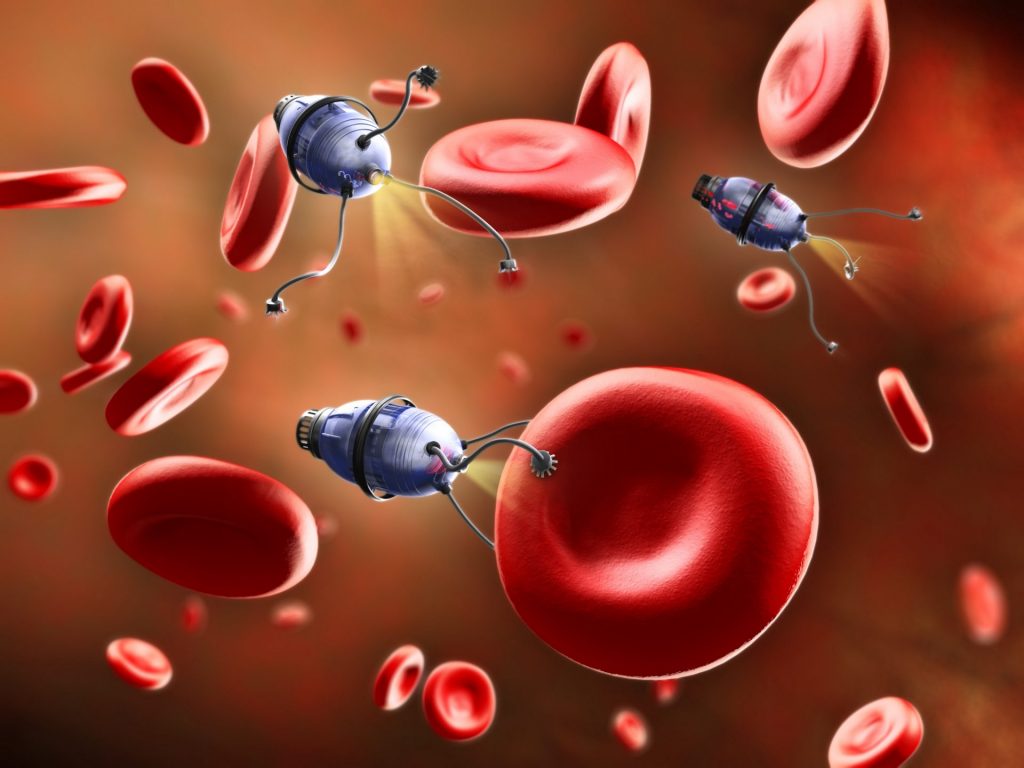

Xenobots have been created in labs back in 2020 from frogs’ stem cells to deliver medical payloads inside the human circulatory system, clean up the diseased arteries or even clean the ocean from plastics when produced in high droves and put into the ocean. They can even exhibit collective behavior in the presence of a swarm of other Xenobots and thus act as some sort of single being.

In the future, clinical applications such as targeted drug delivery Xenobots could be made from a human patient’s own cells, which would bypass the immune response challenges of other kinds of micro-robotic delivery systems. InO-Bot could be used to scrape plaque from arteries and with additional cell types and bioengineering, locate and treat disease. Aside from these immediate practical tasks, the Xenobots could help researchers to understand more about complex cellular behaviors and disease mechanisms.

Even if we controlled Xenobots at absolute precision, which we currently are not able to do. But that is a field at which thousands of researchers are looking currently, whether it’s for delivering nanobots to someone’s brain for enabling high-bandwidth brain-computer interfaces, or people modifying human cells to extend someone’s longevity.

Xenobots are not only for making useful machines. We can imagine programming Xenobots to go out into the environment and collect toxins and clean up, or, we can imagine Xenobots made of human cells that would go through our bodies and collect cancer cells or reshape arthritic joints.